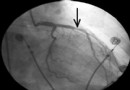

心髒瓣膜病的瓣膜成形手術

瓣膜成形手術需針對所有不同心髒瓣膜病變采用不同修復方法,包括瓣葉部分切除修補術,瓣膜或腱索粘連分離術,腱索縮短或移植術,